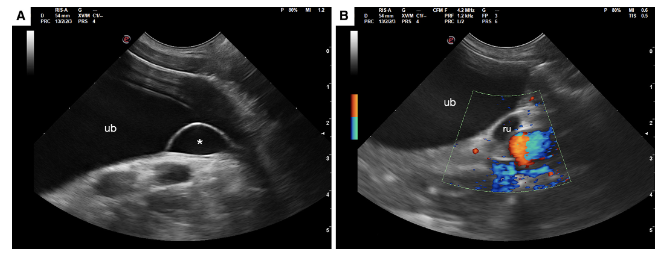

이런식으로 방광 삼각부에 낭성의 물주머니 양상으로 보이는게 전형적인 모양이다.